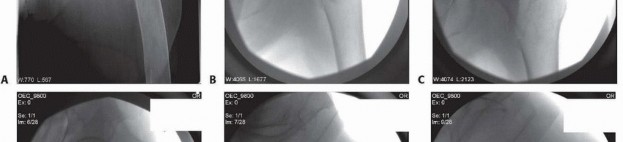

### TECH FIG 4 • Blade plate insertion. A,B. Preoperative AP and lateral radiographs of a type 31-A3 fracture in a 28-year-old man. C. Chisel inserted after femoral head and neck and trochanteric block were secured with lag screws. D. Insertion of blade plate. E. Postoperative AP radiograph. -

### TECH FIG 5 • Proximal femoral locking plate fixation. A,B. Preoperative AP and lateral radiographs of a type 31-A3 fracture in a 27-year-old woman. C. Intraoperative reduction is obtained using reduction clamps, K-wires, retractors, and a femoral distractors (vs. Schanz pin). D,E. Lateral and AP views intraoperatively demonstrating locking plate in place. F. AP radiograph of right hip obtained 1 year postoperatively, demonstrating preservation of length and angulation as well as bony union.